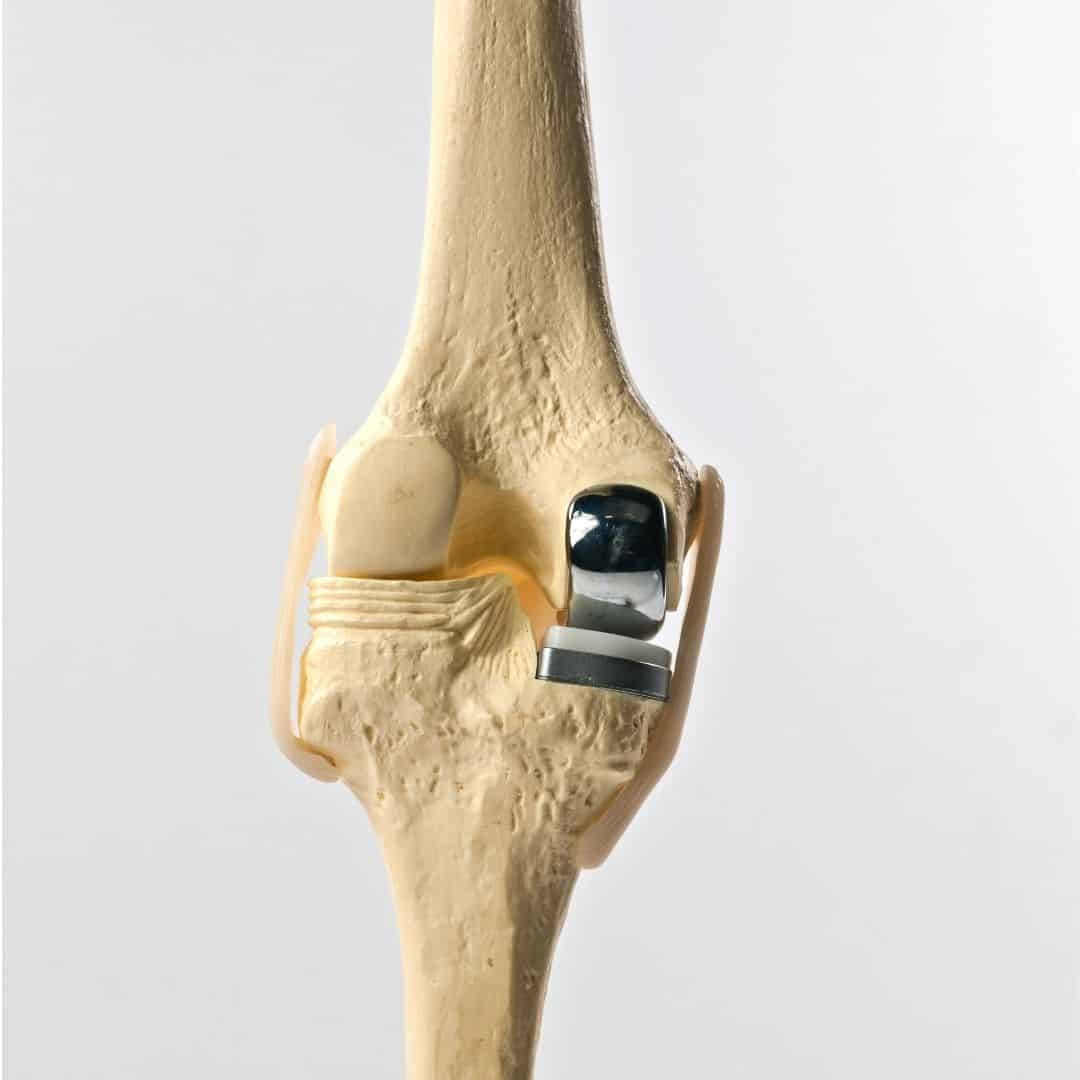

During the surgery, the orthopedic surgeon makes a small incision over the knee and removes the damaged bone and cartilage from the affected compartment. These are then replaced with metal and plastic components designed to mimic the natural movement of the knee. The goal is to relieve pain and improve function while maintaining as much of the natural knee structure as possible. One of the significant advantages of partial knee replacement is that it is less invasive than total knee replacement, resulting in a shorter hospital stay, faster recovery, and less postoperative pain.

Partial and total knee replacements are surgical procedures designed to alleviate pain and restore function in patients with severe knee arthritis, but they differ significantly in their approach and scope. This procedure is less invasive, preserving more of the patient's natural knee structures, including the ligaments. In contrast, total knee replacement involves replacing all three compartments of the knee: the medial, lateral, and patellofemoral (front) compartments. This procedure is recommended for patients with widespread arthritis affecting the entire knee joint. During the surgery, the damaged bone and cartilage are removed and replaced with metal and plastic components designed to mimic the natural movement of the knee.